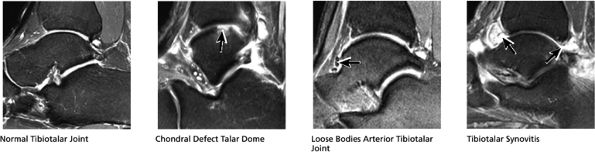

FS PD FSE sequences are performed in all three orthogonal or orthogonal-oblique planes.

Decreasing the FOV or increasing the resolution in the coronal plane allows optimal separation of the distal tibial and talar dome chondral surfaces.

Fat-suppressed PD-weighted fast spin-echo sequences (FS PD FSE) in all three orthogonal planes (Fig. 5.1)

FIGURE 5.1 ● Visualization of tibiotalar articular surfaces using a coronal FS PD FSE sequence. Separation of the tibial and talar chondral surfaces is important in characterizing osteochondral lesions.